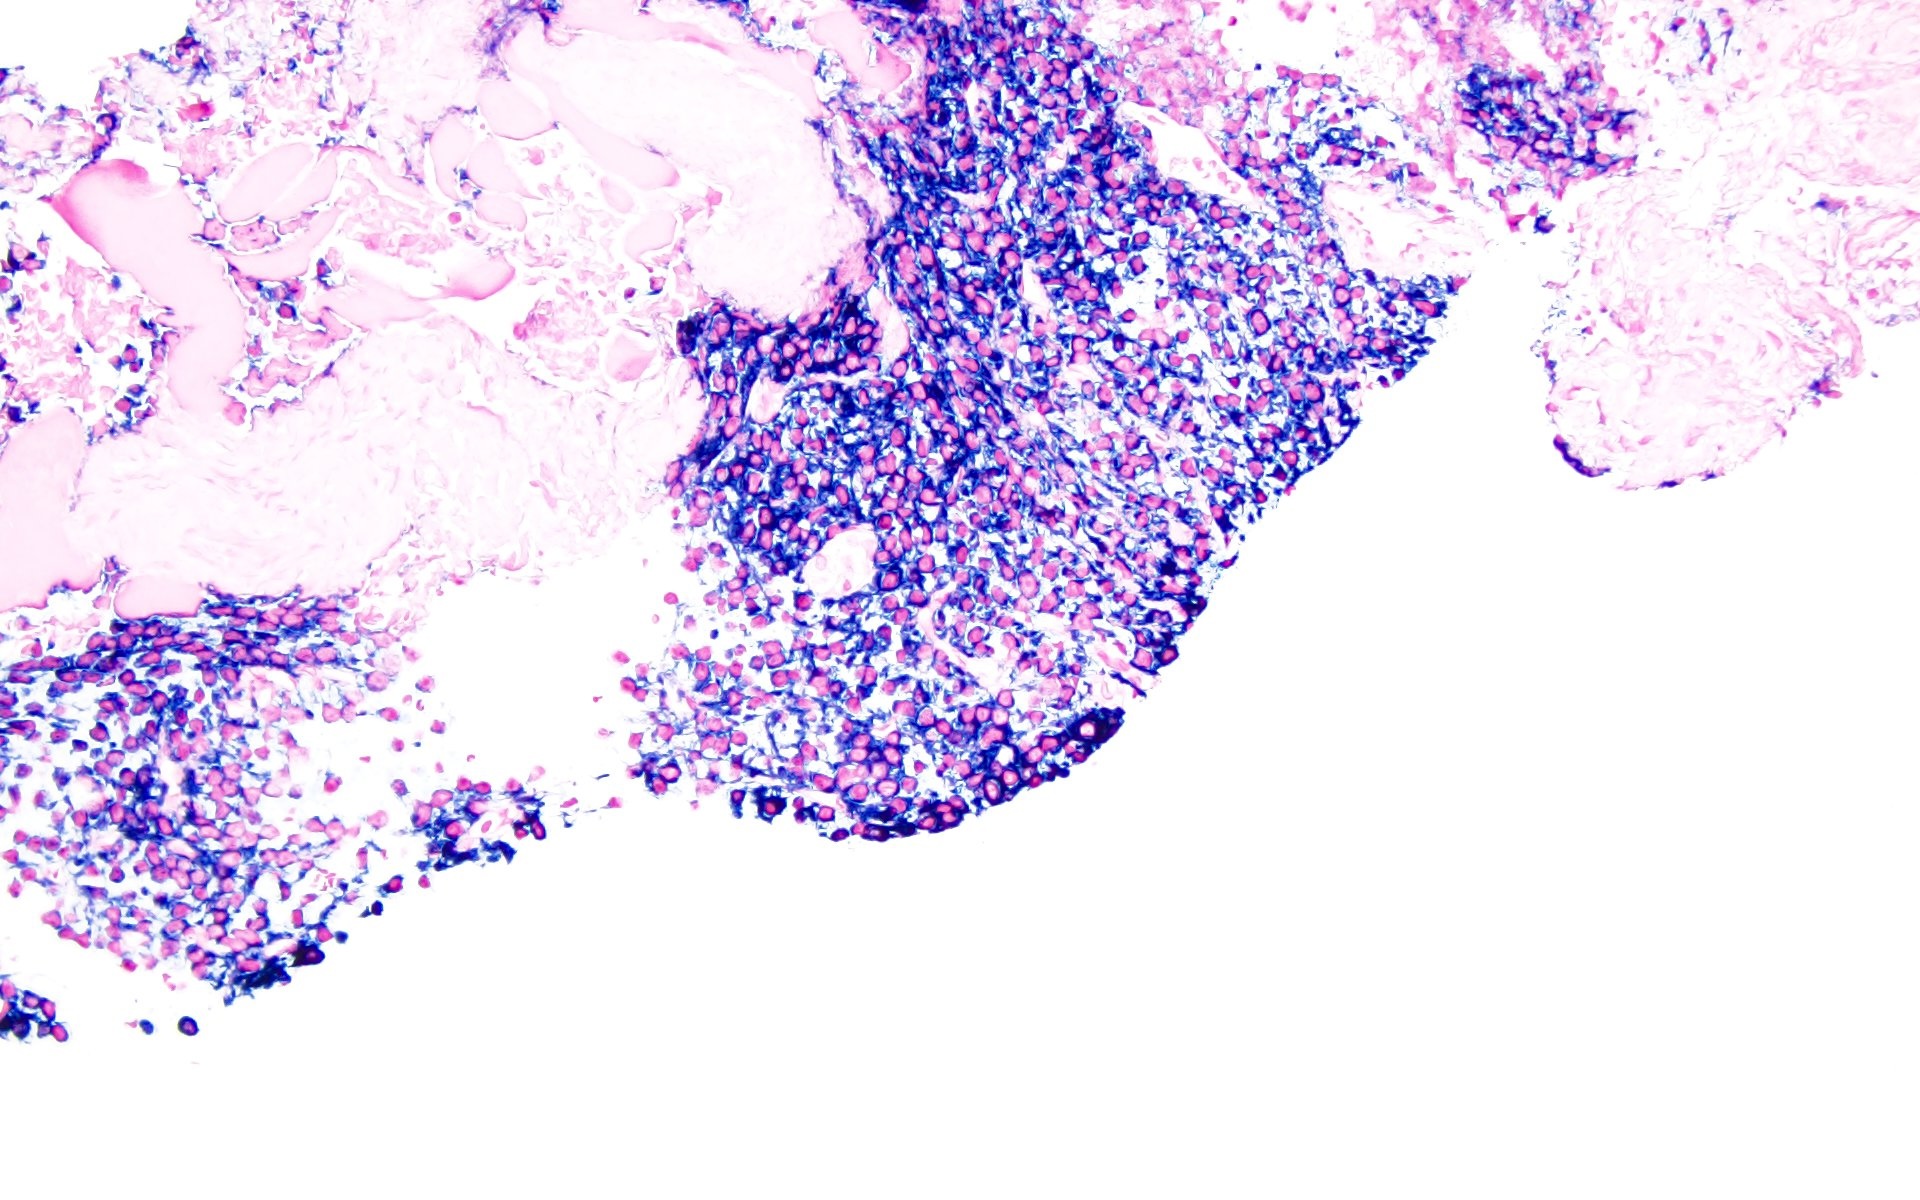

- Sheets of plasma cells with varying morphology ranging from normal appearing to large atypical plasma cells with prominent nucleoli to plasmablastic or anaplastic morphology (Am J Clin Pathol 2001;115:119, J Clin Oncol 2012;30:e91, Skeletal Radiol 2018;47:995)

- Russell or Dutcher bodies may be seen

- Associated amyloid deposition (Ann Diagn Pathol 2015;19:117)

Microscopic (histologic) images

A 43 year old man presents with nasal obstruction and epistaxis. Imaging showed a 2.2 cm nasopharyngeal mass. Nasopharyngeal and bone marrow biopsies were performed (see images above). Which of the following risk factors in this patient increases the chances of progression to multiple myeloma?

B. Bone marrow involvement is present in this case, which increases the risk of progression to multiple myeloma. Answers A, C and D are incorrect because the patient is young and the tumor size is < 5 cm with bland morphology (not plasmablastic / anaplastic), so none of the factors accounted for by these options increase risk of progression to multiple myeloma.